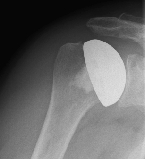

left: X-ray image of an omarthrosis

right: X-ray of a healthy shoulder joint

X-rays can be used to reliably diagnose the extent of joint wear. In the case of severe osteoarthritis, for example, the joint space and the formation of jagged edges (osteophytes) can be detected. If additional damage to the tendons of the shoulder (rotator cuff) is suspected, ultrasound examination (sonography) or magnetic resonance imaging (MRI) can help clarify the situation.